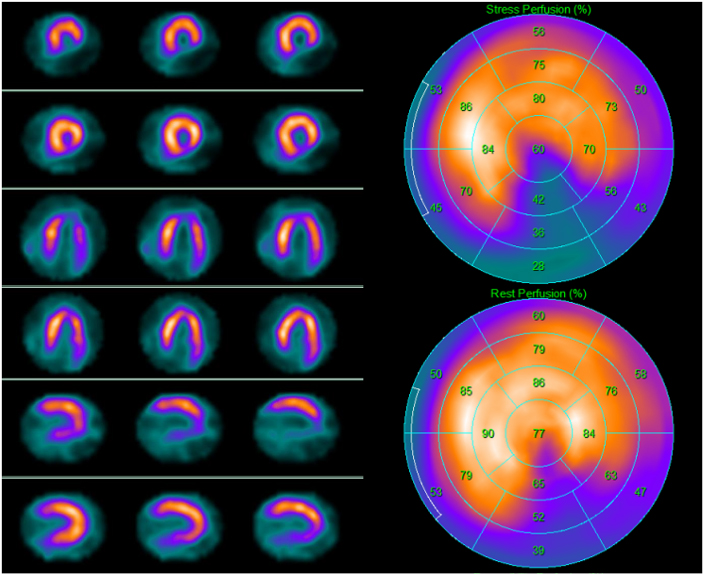

The role of stress testing in preoperative risk assessment of patients before noncardiac surgery has been extensively demonstrated [68, 69, 70]. Moderate to severe myocardial ischemia is a sensitive marker of increased risk of perioperative MACE. Normal SPECT findings portend a high negative predictive value for perioperative cardiac events, while detection of scars has a low positive predictive value. Due to the underlying CAD, however, long-term prognosis is worse in these patients (Fig. 4).

Fig. 4.A 69-year-old asymptomatic man with multiple cardiovascular risk factors underwent 99mTc-tetrofosmin cardiac single photon emission computed tomography (SPECT) screening for myocardial ischemia before kidney transplantation. SPECT revealed a partially reversible inferior defect. Subsequent invasive coronary angiography revealed severe stenosis of the posterior descending artery, which was treated with angioplasty. Left side top row: stress-rest short axis; stress-rest horizontal long axis; stress-rest vertical long axis; right side: polar map of stress (upper image) and rest perfusion (lower image).

In a meta-analysis of ten studies with pharmacological stress SPECT, the 30-day MACE rates were 1% in patients with normal test results, 7% and 9% in those with fixed and reversible perfusion defects, respectively, with a higher event rate in those with at least two reversible defects [71].